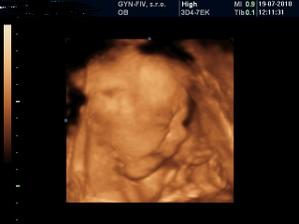

krasne brusinko tehulkovske 🙂

ziza55 neboj ked sa maly narodi, nebudes ho chciet vymenit ani za babu, ja som tiez chcela dievku, od začiatku som tusila ze bude chalan a nemenila by som 🙂 tie jeho kukadla a usmev ... to je paradny pocit